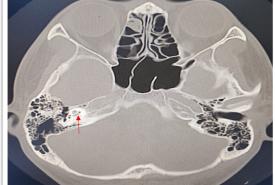

Labyrinthitis Ossificans Post COVID Vaccination

Case Report 27 Jan, 2025